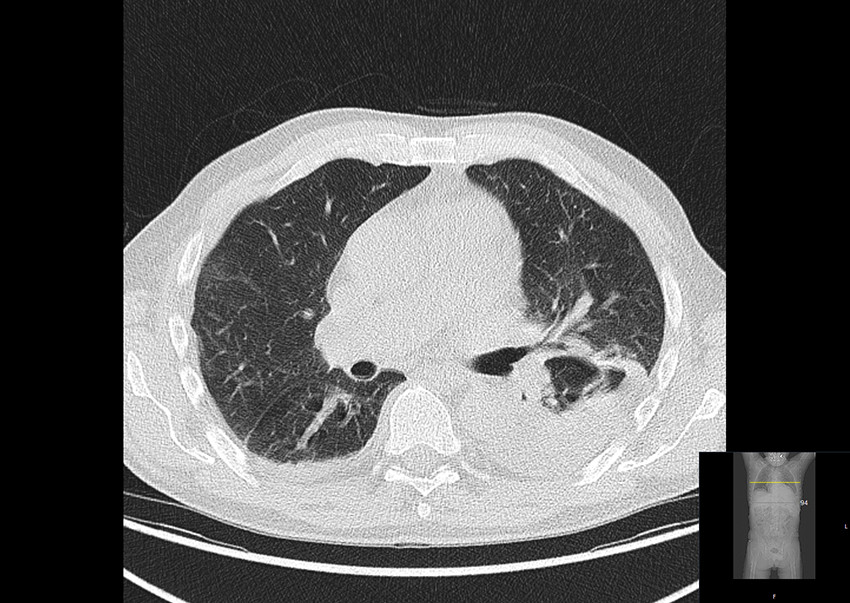

PET-CT-undersøkelse med ¹⁸F-fluordeoksyglukose (¹⁸F-FDG) utført ved innleggelsen viste økt opptak av ¹⁸F-fluordeoksyglukose i torakalaorta, buekaravganger og perikard (figur 1).

Det var også økt opptak av ¹⁸F-fluordeoksyglukose i benmarg og lymfeknuter, som ble vurdert å være reaktive forandringer. I tillegg ble det funnet et infiltrat i venstre lunges underlapp og pleuravæske (figur 2).

Tilstanden ble oppfattet som ekstrakraniell kjempecellearteritt. Diagnosen ble stilt på bakgrunn av følgende symptomer og funn: redusert allmenntilstand, smerter i brystet, hodet og kjeveledd, veggfortykkelse i venstre arteria subclavia, økt opptak av ¹⁸F-fluordeoksyglukose i store blodårer og forhøyede verdier av akuttfasereaktanter.